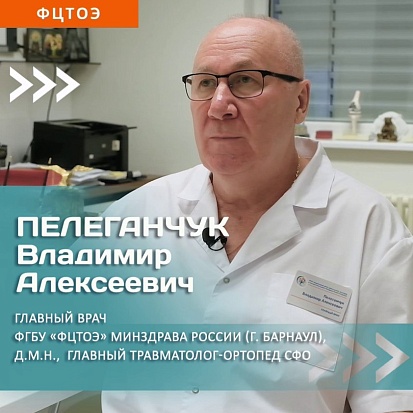

ФЕДЕРАЛЬНЫЙ ЦЕНТР ТРАВМАТОЛОГИИ, ОРТОПЕДИИ И ЭНДОПРОТЕЗИРОВАНИЯ

Факторы достижения исторического максимума 2023